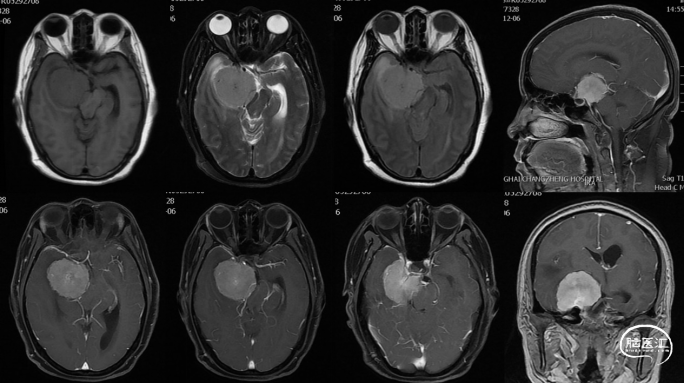

作者:宁波

患者,男,54岁。主诉:头痛半月,加重3天。现病史:患者半月前突发头痛,呈持续性全头部胀痛,与活动及体位改变无关,无头晕、恶心、呕吐,无肢体乏力、抽搐,患者未予重视,自行服用止痛药,无明显好转;3天前患者自觉头痛较前有加重遂来前往外院就诊,头颅CT示:右侧额叶占位。为求进一步诊治,收入我科。